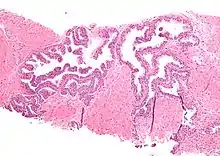

Micrograph showing high-grade prostatic intraepithelial neoplasia. H&E stain.

Microscopically, PIN is a collection of irregular, atypical epithelial cells. The architecture of the glands and ducts remains normal. The epithelial cells proliferate and crowding results in a pseudo-multilayer appearance. They remain fully contained within a prostate acinus (the berry-shaped termination of a gland, where the secretion is produced) or duct. The latter can be demonstrated with special staining techniques (immunohistochemistry for cytokeratins) to identify the basal cells forming the supporting layer of the acinus. In prostate cancer, the abnormal cells spread beyond the boundaries of the acinus and form clusters without basal cells. In HGPIN, the basal cell layer is disrupted but present. PIN is primarily found in the peripheral zone of the prostate (75-80%), rarely in the transition zone (10-15%) and very rarely in the central zone (5%), a distribution that parallels the zonal distribution for prostate carcinoma.[7]